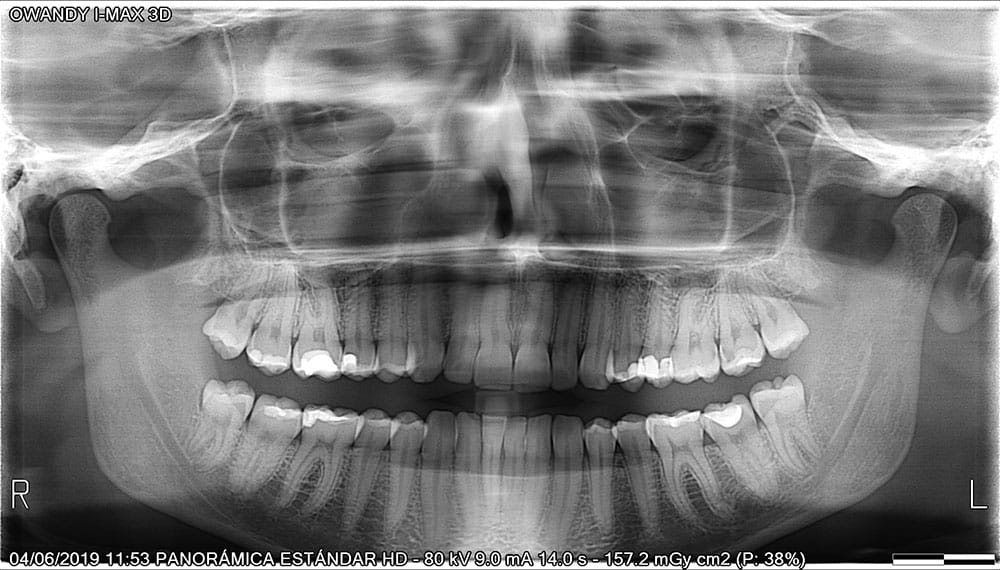

Mala praxis en radiografías dentales

Errores en Radiografías Dentales: Un Riesgo en el Diagnóstico y Tratamiento

Las radiografías dentales son fundamentales para un diagnóstico preciso y la planificación de tratamientos. Sin embargo, una mala praxis en su interpretación o realización puede llevar a errores graves, como diagnósticos incorrectos, tratamientos innecesarios o la omisión de patologías importantes.

Entre los errores más comunes están la mala calidad de la imagen, exposición innecesaria a radiación, interpretación errónea de caries o infecciones, y fallos en la identificación de estructuras anatómicas. Estas negligencias pueden derivar en extracciones innecesarias, colocación incorrecta de implantes o la progresión de enfermedades sin detectar.